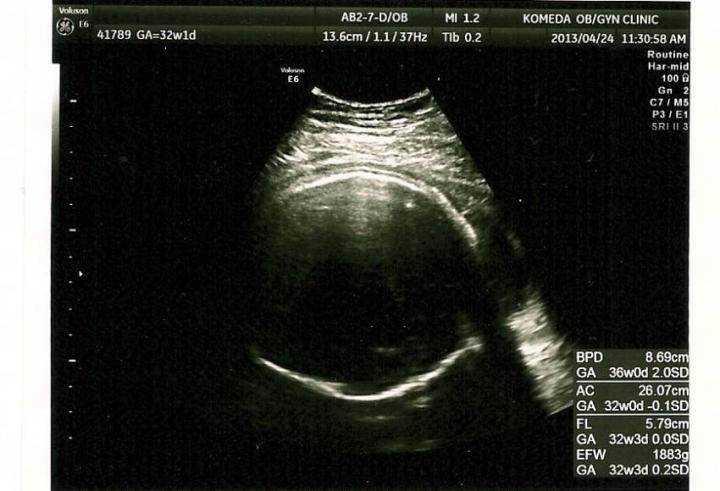

そして エコーも主人立会いの下、性別の再確認☆

しっかり(笑)男の子でした(^^)

体重も 1900くらいとすくすくと成長していました(^^)

まだ 32週だし・・・とかのんきにしていたのですが、赤ちゃんが すっぽり頭を入れたり、出てくる準備のためか 恥骨が緩んできているみたいです(;;)